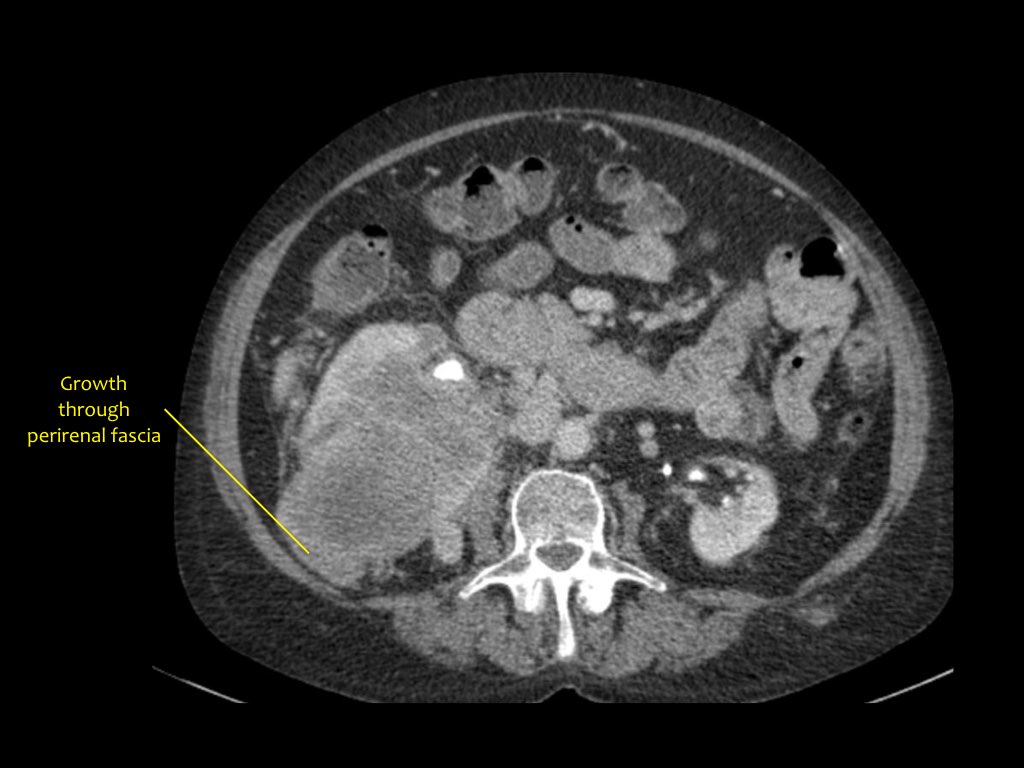

Phân giai đoạn RCC

RCC có thể xâm lấn mỡ quanh thận vượt qua cân thận và có thể lan vào tĩnh mạch thận, tĩnh mạch chủ dưới (IVC) hoặc tuyến thượng thận cùng bên.

Đối với phẫu thuật viên, điều quan trọng là cần biết có huyết khối u trong IVC hay không và liệu huyết khối có lan vào lồng ngực trên cơ hoành hay không (cần có phẫu thuật viên lồng ngực trong ca mổ).

Khoảng 25% bệnh nhân đã có di căn tại thời điểm chẩn đoán.